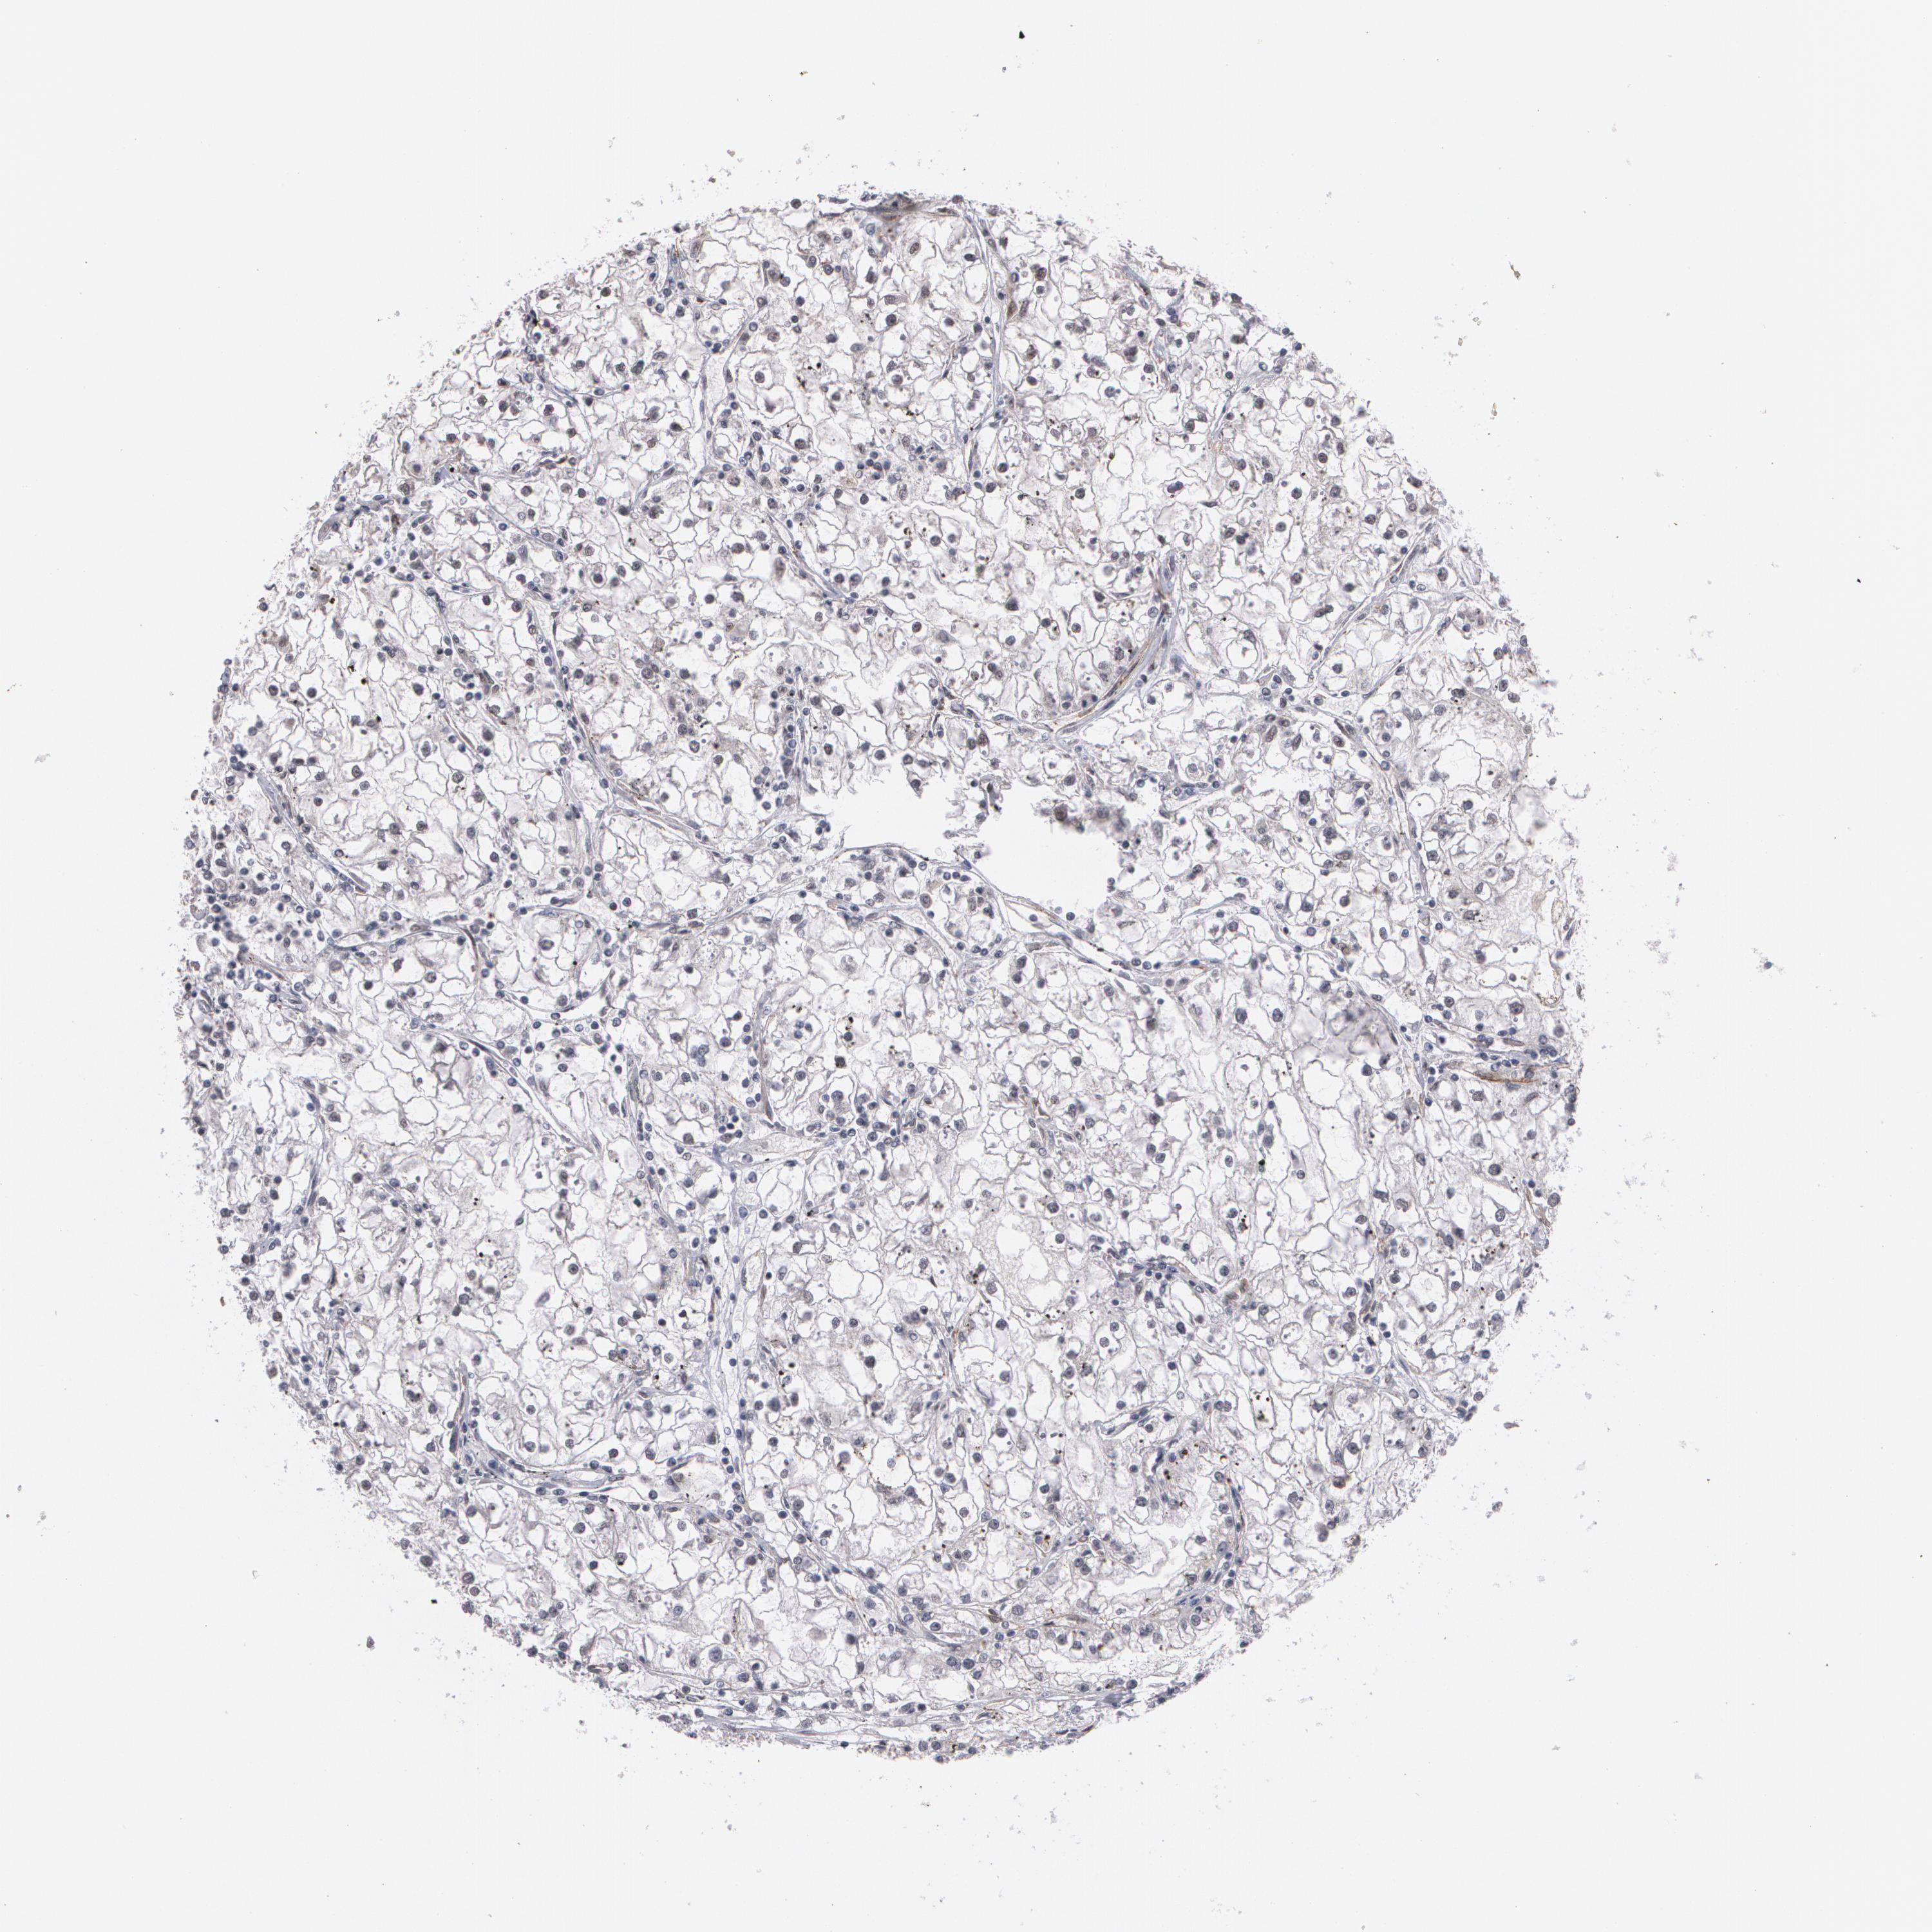

KIDNEY RENAL CLEAR CELL CARCINOMA (VALIDATION) - Interactive survival scatter ploti

The Survival Scatter plot shows the clinical status (i.e. dead or alive) for all individuals in the patient cohort, based on the same data that underlies the corresponding Kaplan-Meier plots. Patients that are alive at last time for follow-up are shown in blue and patients who have died during the study are shown in red.

The x-axis shows the expression levels (FPKM) of the investigated gene in the tumor tissue at the time of diagnosis. The y-axis shows the follow-up time after diagnosis (years). Both axes are complimented with kernel density curves demonstrating the data density over the axes. The top density plot shows the expression levels (FPKM) distribution among dead (red) and alive patients (blue). The right density plot shows the data density of the survived years of dead patients with high and low expression levels respectively, stratified using the cutoff indicated by the vertical dashed line through the Survival Scatter plot. This cutoff is automatically defined based on the FPKM cutoff that minimizes the p-score. The cutoff can be changed by dragging the vertical line or by entering a cutoff value in the square labeled "Current cut-off".

Under the Survival Scatter plot the p-score landscape (black curve; left axis) is shown together with dead median separation (red curve; right axis). Dead median separation is the difference in median mRNA expression between patients who have died with high and low expression, respectively. It is calculated as follows: median FPKM expression of dead patients with high expression - median FPKM expression of dead patients with low expression. This is intended to aid the user in visually exploring custom cutoffs and the associated p-scores and dead median separation.

Individual patient data is displayed and can be filtered by clicking on one or more of the category buttons on the top of the page. Categories describing expression level and patient information include: high, low, alive, dead, female, male and tumor stages. The scale of the x-axis can be toggled between linear and log-scale by clicking on the "x log" button. Mouse-over function shows TCGA ID, patient information and mRNA expression (FPKM) for each patient.

& Survival analysisi

Kaplan-Meier plots summarize results from analysis of correlation between mRNA expression level and patient survival. Patients were divided based on level of expression into one of the two groups "low" (under cut off) or "high" (over cut off). X-axis shows time for survival (years) and y-axis shows the probability of survival, where 1.0 corresponds to 100 percent.

ZNF75A is potential prognostic, high expression is favorable in Kidney Renal Clear Cell Carcinoma (validation)

Best expression cut offi

Based on the FPKM value of each gene, patients were classified into two groups and association between prognosis (survival) and gene expression (FPKM) was examined. The best expression cut-off refers the FPKM value that yields maximal difference with regard to survival between the two groups at the lowest log-rank P-value. Best expression cut-off was selected based on survival analysis .

When clicking on this number, the vertical dashed line indicating cut-off, the interactive survival plot, and the Kaplan-Meier curve will be adjusted to show results based on the best expression cut-off.

: 7.27

TCGA RNA samplesi

RNA-seq data is reported as average FPKM (number Fragments Per Kilobase of exon per Million reads), generated by the The Cancer Genome Atlas (TCGA) .

Normal distribution across the dataset is visualized with box plots, shown as median and 25th and 75th percentiles. Points are displayed as outliers if they are above or below 1.5 times the interquartile range. FPKM values of the individual samples are presented next to the box plot.

Average pTPM 8.2

Number of samples 100